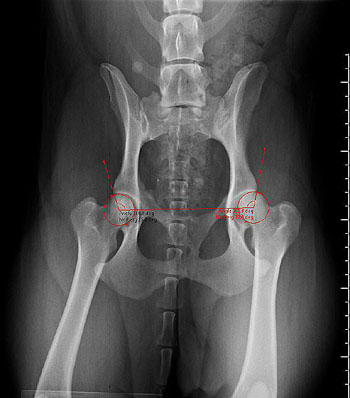

Until recently, vets have been required to submit films to the Schemes and the BVA scrutineers take the necessary measurements manually, whilst viewing the films on a light box.

Digital x-rays can now be submitted on DICOM CDs and, once checked against the accompanying certificate, uploaded to the system using a Visbion workstation. The Visbion software displays the images on dual high resolution monitors and provides the scrutineers with specially developed tools to take accurate assessments and measurements. The image can then be securely archived.